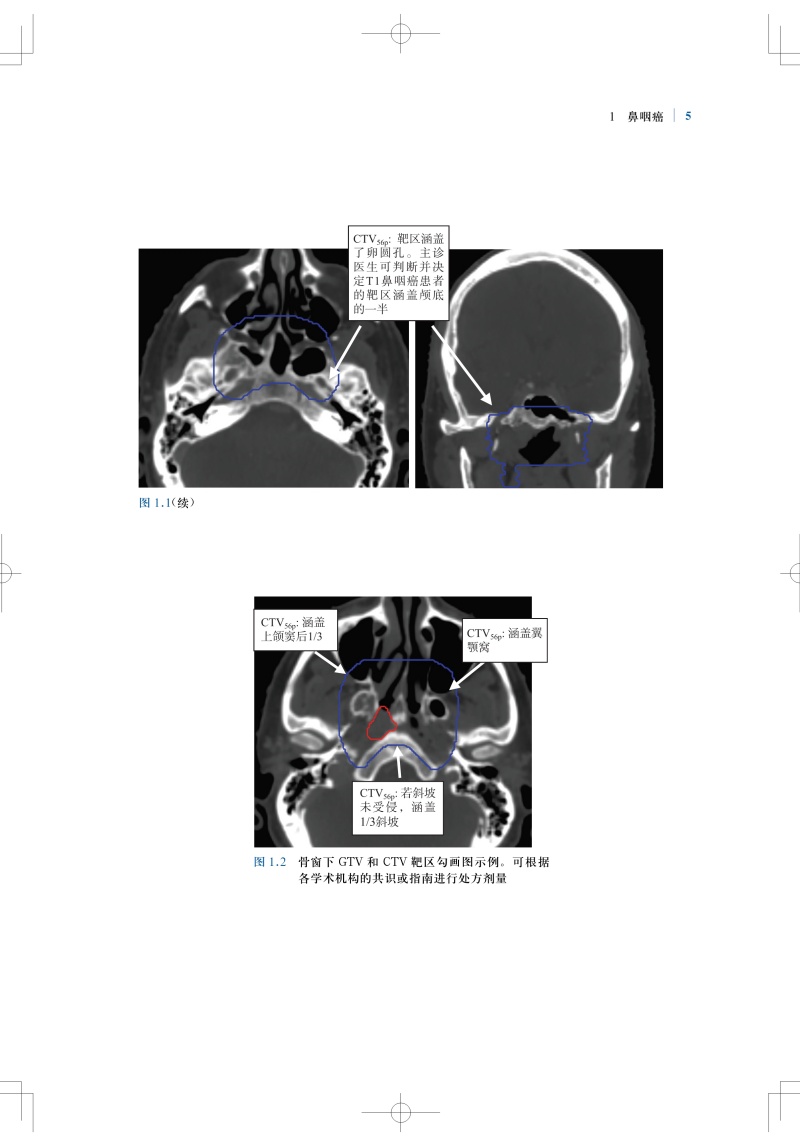

肿瘤放射治疗靶区勾画与射野设置是疗效的基石,精准的靶区范围的确定和勾画可确保肿瘤患者的放疗效果。全书结合大量影像图片,按章分别详细介绍了各种常见病变的具有临床依据的精确的CTV勾画和指南,包括鼻咽癌、甲状腺癌、早期乳腺癌、肺癌、直肠癌、前列腺腺癌、膀胱癌等;并对相关的淋巴引流区解剖进行了勾画,且逐层显示并说明注意事项。本书内容实用,可为放疗医师对常见肿瘤进行适形放疗和调强放疗时的靶区勾画及放射野设置提供指导和参考。